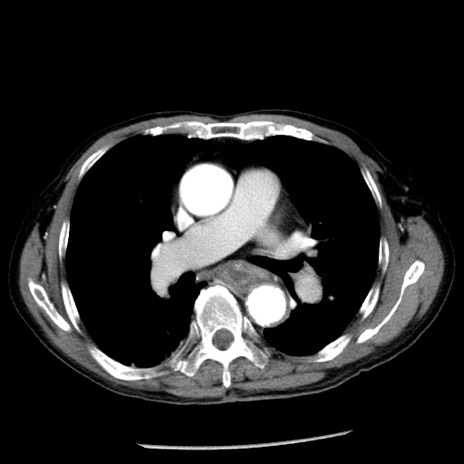

症例26(横断像)

冠状断像

【症例】80歳代男性

【主訴】嘔吐

【現病歴】昨晩2回嘔吐あり、今朝になっても嘔吐あり。来院。

【既往歴】胃潰瘍

【身体所見】意識清明、BT 37.6℃、BP 166/95mmHg、HR 100bpm、SpO2 97%、腹部:平坦・軟、腸蠕動音聴取良好、圧痛なし。

【データ】WBC 21900、CRP 1.46